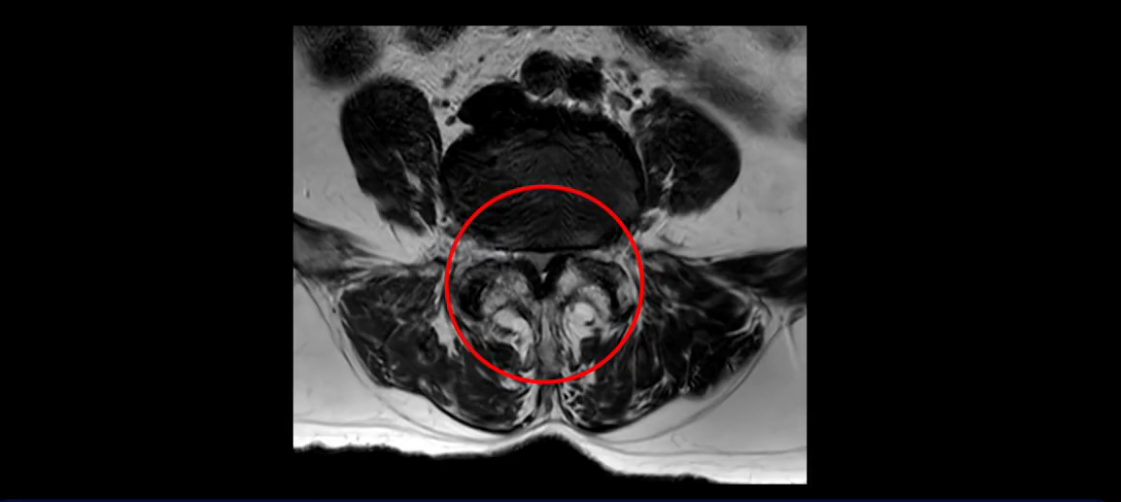

먼저 이분 MRI를 보고 자세히 설명해 드린 후 어떻게 허리 여러 마디에서 협착과 전방전위로 신경이 심하게 눌려 보이는 환자가 수술 없이 좋아질 수 있는지, 또 치료는 어떻게 하는지 설명해 드리겠습니다.

또 척추관협착도 매우 심합니다.

척추관이 심하게 좁아져 있습니다.

이렇게 신경 구멍들이 좁아져 있고 신경이 눌리니까 엉덩이와 다리가 너무 저리고 아파서 아예 일어서질 못하니까 휠체어를 타고 병원에 내원하셨는데요. 그럼 어떻게 이분처럼 신경이 눌려있는 환자분들을 수술 없이 치료해서 잘 걷게 만들고 엉덩이와 다리가 저리고 아픈 증상이 사라지게 할까요? 지금부터 설명해 드립니다.